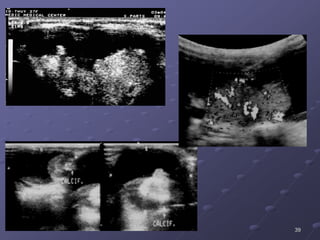

VOÂI HOAÙ / PGH

 86,7% laø nhaân ñaëc echo keùm, khi lôùn hôn 1 cm nhaân trôû

neân khoâng ñoàng nhaát, giôùi haïn khoâng roõ, 50% coù vi voâi hoùa,

ít thaáy ñöôïc hình daïng nhuù trong nang.

39